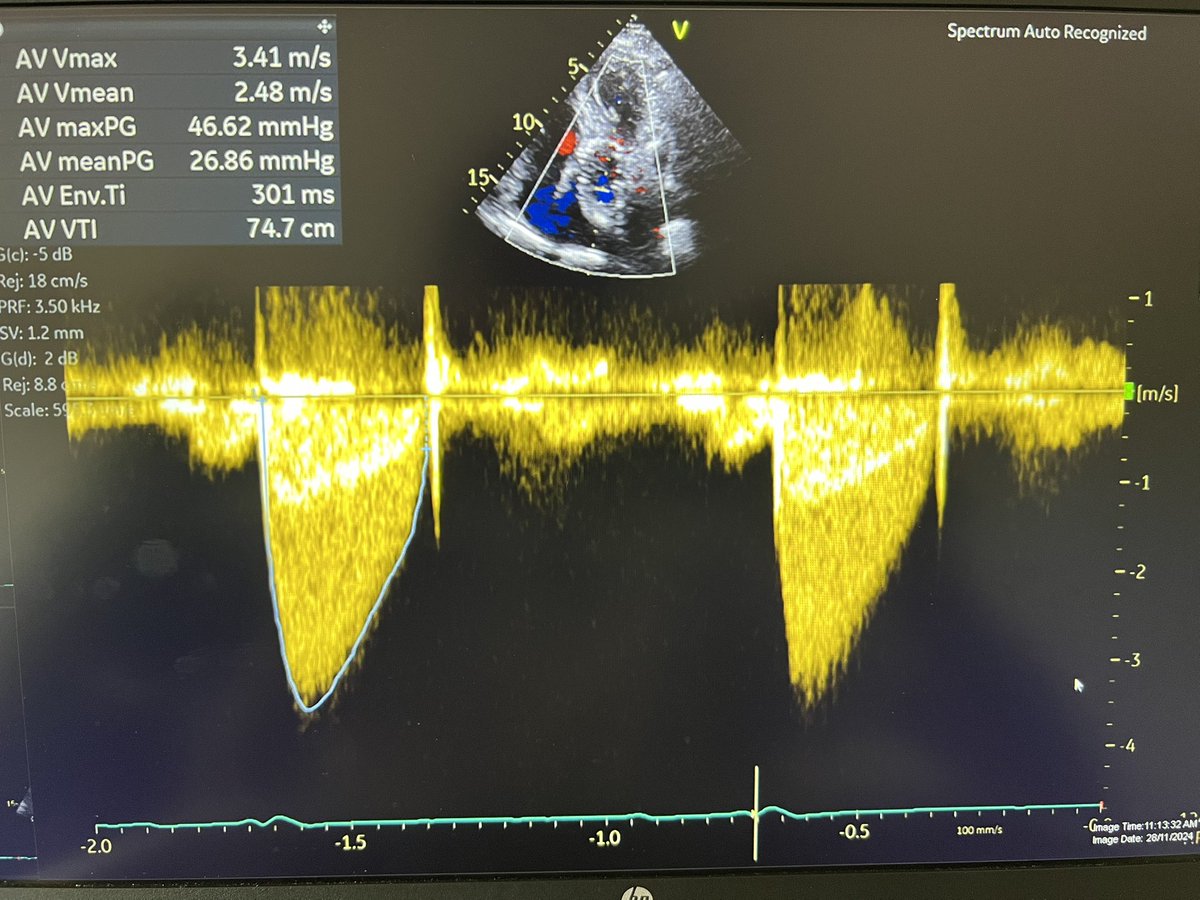

Confusing case of mod/sev AS.

Valve looks calcified but the gradients are discordant . Keen to know everyone’s thoughts @Becho2106 @echoguru @KemalogluOz @sturwohld @RobChamb87 @NMerke @echo_stepbystep @BeardedHeartDoc @kaznegishi 1/

@echoguru @BeardedHeartDoc @BiancaJudyC @KemalogluOz @sturwohld @RobChamb87 @NMerke @echo_stepbystep @kaznegishi I agree, there's movement of the valve which is absent in a severe AS. Is the GLS reduced? Subclinical reduction in systolic function will also reduce the forward flow through the AV